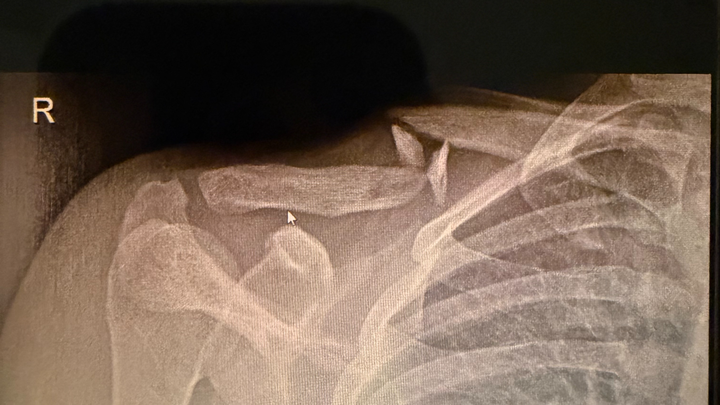

We are reaching out to community to raise funds for our deeply loved friend and community member Cewa (@anommalouss). On Jan 11, Cewa got into a bike accident that left their collarbone broken. Cewa is a private care assistant and works for disabled people, physically lifting and transferring folks multiple times a day. They also work under the table and do not qualify for any governmental assistance because of that. They do not receive sick pay as well. They are about to undergo surgery and cannot work for 2 months, potentially more, due to the nature of this injury and their line of work.